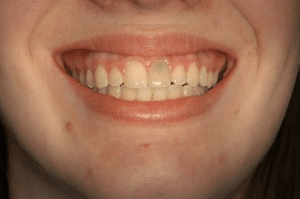

This twenty three year old woman presented to us as a teenager with her maxillary central incisor failing. The tooth was replaced with a bone graft and a removable appliance, which provided a temporary replacement tooth during her teenage years. After waiting an appropriate amount of time until she had stopped growing, we inserted the implant, itself, using a special CT Scan generated surgical guide so that it was placed at the right depth and angulation. Her dentition has been rejuvenated.

The timing of implant placement is crucial, especially in young patients. We waited until skeletal growth was complete to ensure the implant would integrate properly and maintain its position for decades. The use of guided surgery with the CT Scan ensured that the implant was positioned exactly right, allowing for a natural-looking crown that perfectly complements her smile.

Before: Failing maxillary central incisor

After: Rejuvenated dentition with natural-looking implant crown